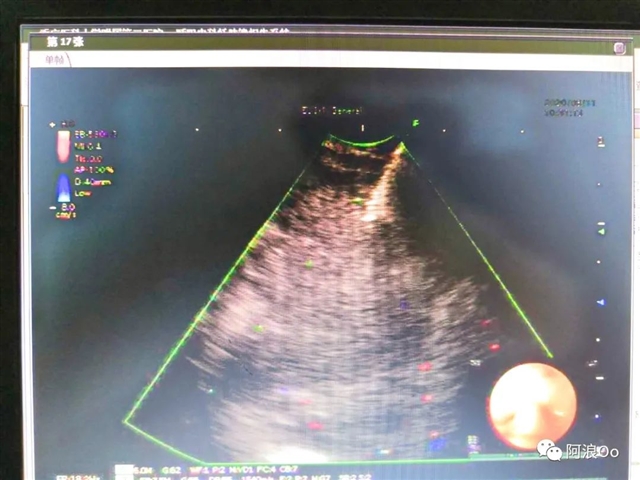

电刀辅助下经气管纵隔活检钳取活检技术(Cautery Assist Transbronchial For cep Biopsy,Ca-TBFB):超声支气管镜引导,经过气管软骨环用针形电刀切开气管粘膜进入纵隔,以活检钳进行纵隔钳取活检。相对于传统TBNA和eBUS-TBNA,能够取得大块组织标本,对于纵隔良性疾病、淋巴瘤具有明显优势。淋巴结坏死明显,多次eBUS-TBNA拿不到病理依据,可以作为备选技术。

擅长于呼吸内科疑难危重病人的诊治,尤其在晚期肺癌的微创介入治疗及肺部微小结节的诊治方面有较为深入的研究。拓展eBUS(超声支气管镜)的深入应用,首先在国内开展电刀辅助下纵膈活检钳取活检(Ca-TBFB)技术, 在国内较早开展超声支气管镜引导下纵膈粒子植入消融技术,解决了众多纵膈疑难疾病的诊治问题。先后发表SCI及CSCD论文10余篇,以编委身份参与人民卫生出版社《内科学》教材一部